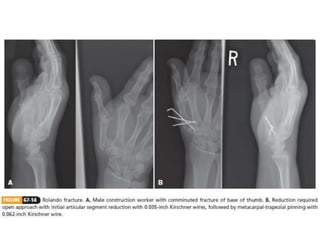

Carpometacarpal (CMC) Fractures

• The normal ROM at the thumb CMC joint

• 50 degrees of flexion-extension

• 40 degrees of abduction-adduction

• 15 degrees of pronation-supination.

Carpometacarpal (CMC) Fractures •The normal ROM at the thumb CMC joint • 50 degrees of flexion-extension • 40 degrees of abduction-adduction • 15 degrees of pronation-supination.